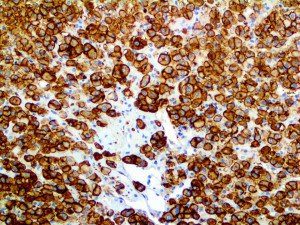

The first cytokines released are interleukin 1β (IL-1β) and tumor necrosis factor-α (TNF-α), which attract a variety of circulating white blood cells (WBCs) to the infection site, including neutrophils, monocytes, macrophages, and natural killer (NK) cells. This response, along with the antipathogenic chemicals released by these cells (i.e., complement), comprise the innate immune response. These cells directly attack the invading pathogen and also release additional cytokines, chief among them interleukin-1 and 6 (IL-6). IL-6 is essential for invoking the adaptive immune response, which calls T-cells, B-cells, and T helper (Th) cells to the infection site. IL-6 also stimulates further recruitment, proliferation and activation of macrophages.

It is the ICU physician who is most likely to witness one of the deadliest manifestations of the abnormal immunological response, the cytokine storm syndrome (CSS). This response is also referred to by some as the cytokine release syndrome (CRS). CSS is characterized by continuous activation and expansion of macrophage and lymphocyte populations, which secrete large amounts of cytokines, causing the cytokine storm. This massive cytokine release is akin to hemophagocytic lymphohistiocytosis (HLH) disease, a syndrome characterized by initial unchecked and persistent activation of cytotoxic T lymphocytes and NK cells.

This activation induces inflammatory monocytes to highly express IL-6, starting a localized and then systemic cascade effect that results in hyperproduction of IL-6, which accelerates the inflammatory process. Because IL-6 also increases vascular permeability, excessive levels cause blood vessels to become very leaky. This, along with clotting factors released from vascular endothelial cells, stimulates the coagulation cascade, resulting in microthrombosis (tiny clots), which leads to ischemia and tissue death of the kidney, intestines, heart, liver, brain and extremities.